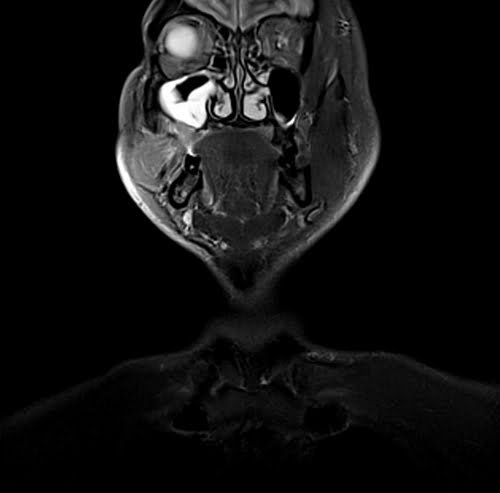

Neck MRI coronal STIR images